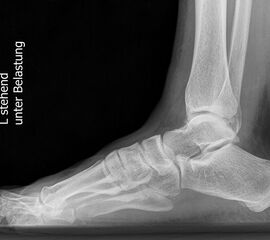

Standard ist die belastete Röntgenaufnahme des Fußes dorso-plantar und seitlich. Günstig ist eine Röhrenkippung von 10°-20°, um die Gelenke der Lisfranc-Linie einsehen zu können.

Ergänzend kann eine Schrägaufnahme hilfreich sein. Bei Metatarsalgien oder Pathologien der Sesambeine liefert die Sprinteraufnahme zusätzliche Informationen. Bei einer Pes planovalgus Fehlstellung wird ergänzend ein Saltzman view durchgeführt.